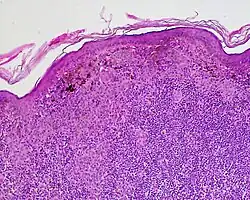

Halo nevus is a mole that is surrounded by a pale ring or 'halo'.[1] It is generally noticed in the summer, when surrounding skin tans, and usually occurs on the chest, but can be anywhere.[1] There may be one or, more typically, several.[2] Onset is usually in teenagers and young adults.[1][3] It typically follows a pattern of appearing at first as a dark mole surrounded by a halo before the nevus fades and disappears.[1] A single halo-nevus-like lesion appearing in an older adult may be a melanoma.[1]

Halo nevi are also known as Sutton's nevi, or leukoderma acquisitum centrifugum.[2] Halo nevi are named such because they are a mole (nevus) that is surrounded by an area of depigmentation that resembles a halo.

The formation of a halo surrounding a nevi is believed to occur when certain white blood cells called CD8+ T lymphocytes destroy the pigment-producing cells of the skin (melanocytes).[4] The cause for the attack is unknown.[5]